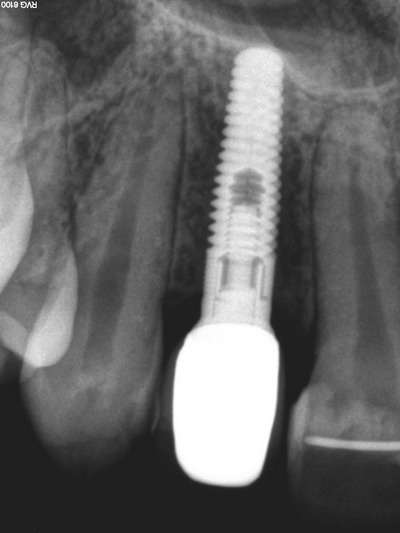

Implants dentaires remplaçant des dents unitaires

Implant dentaire postérieur

Couronnes sur implants dentaires